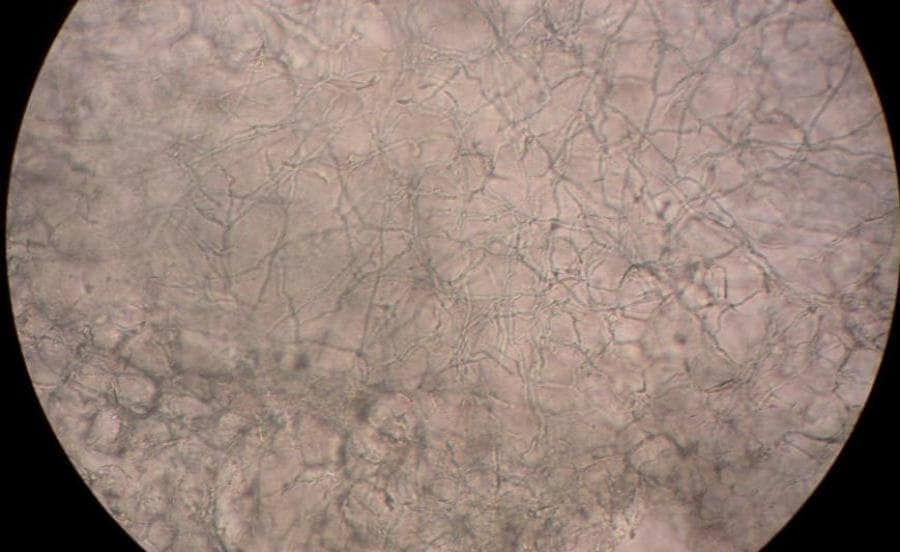

Behandeling van schimmelinfecties

Er zijn twee soorten schimmelinfecties. De meeste zijn onschuldig, goed behandelbaar en bevinden zich op je huid, in huidplooien of slijmvliezen. Bij ernstigere, invasieve infecties dringt de schimmel diep door in het lichaam en veroorzaakt daar levensbedreigende infecties in de organen. Beide typen schimmelinfecties worden behandeld met antimycotica: geneesmiddelen met een schimmelwerende (fungistatische) of schimmeldodende (fungicide) werking.